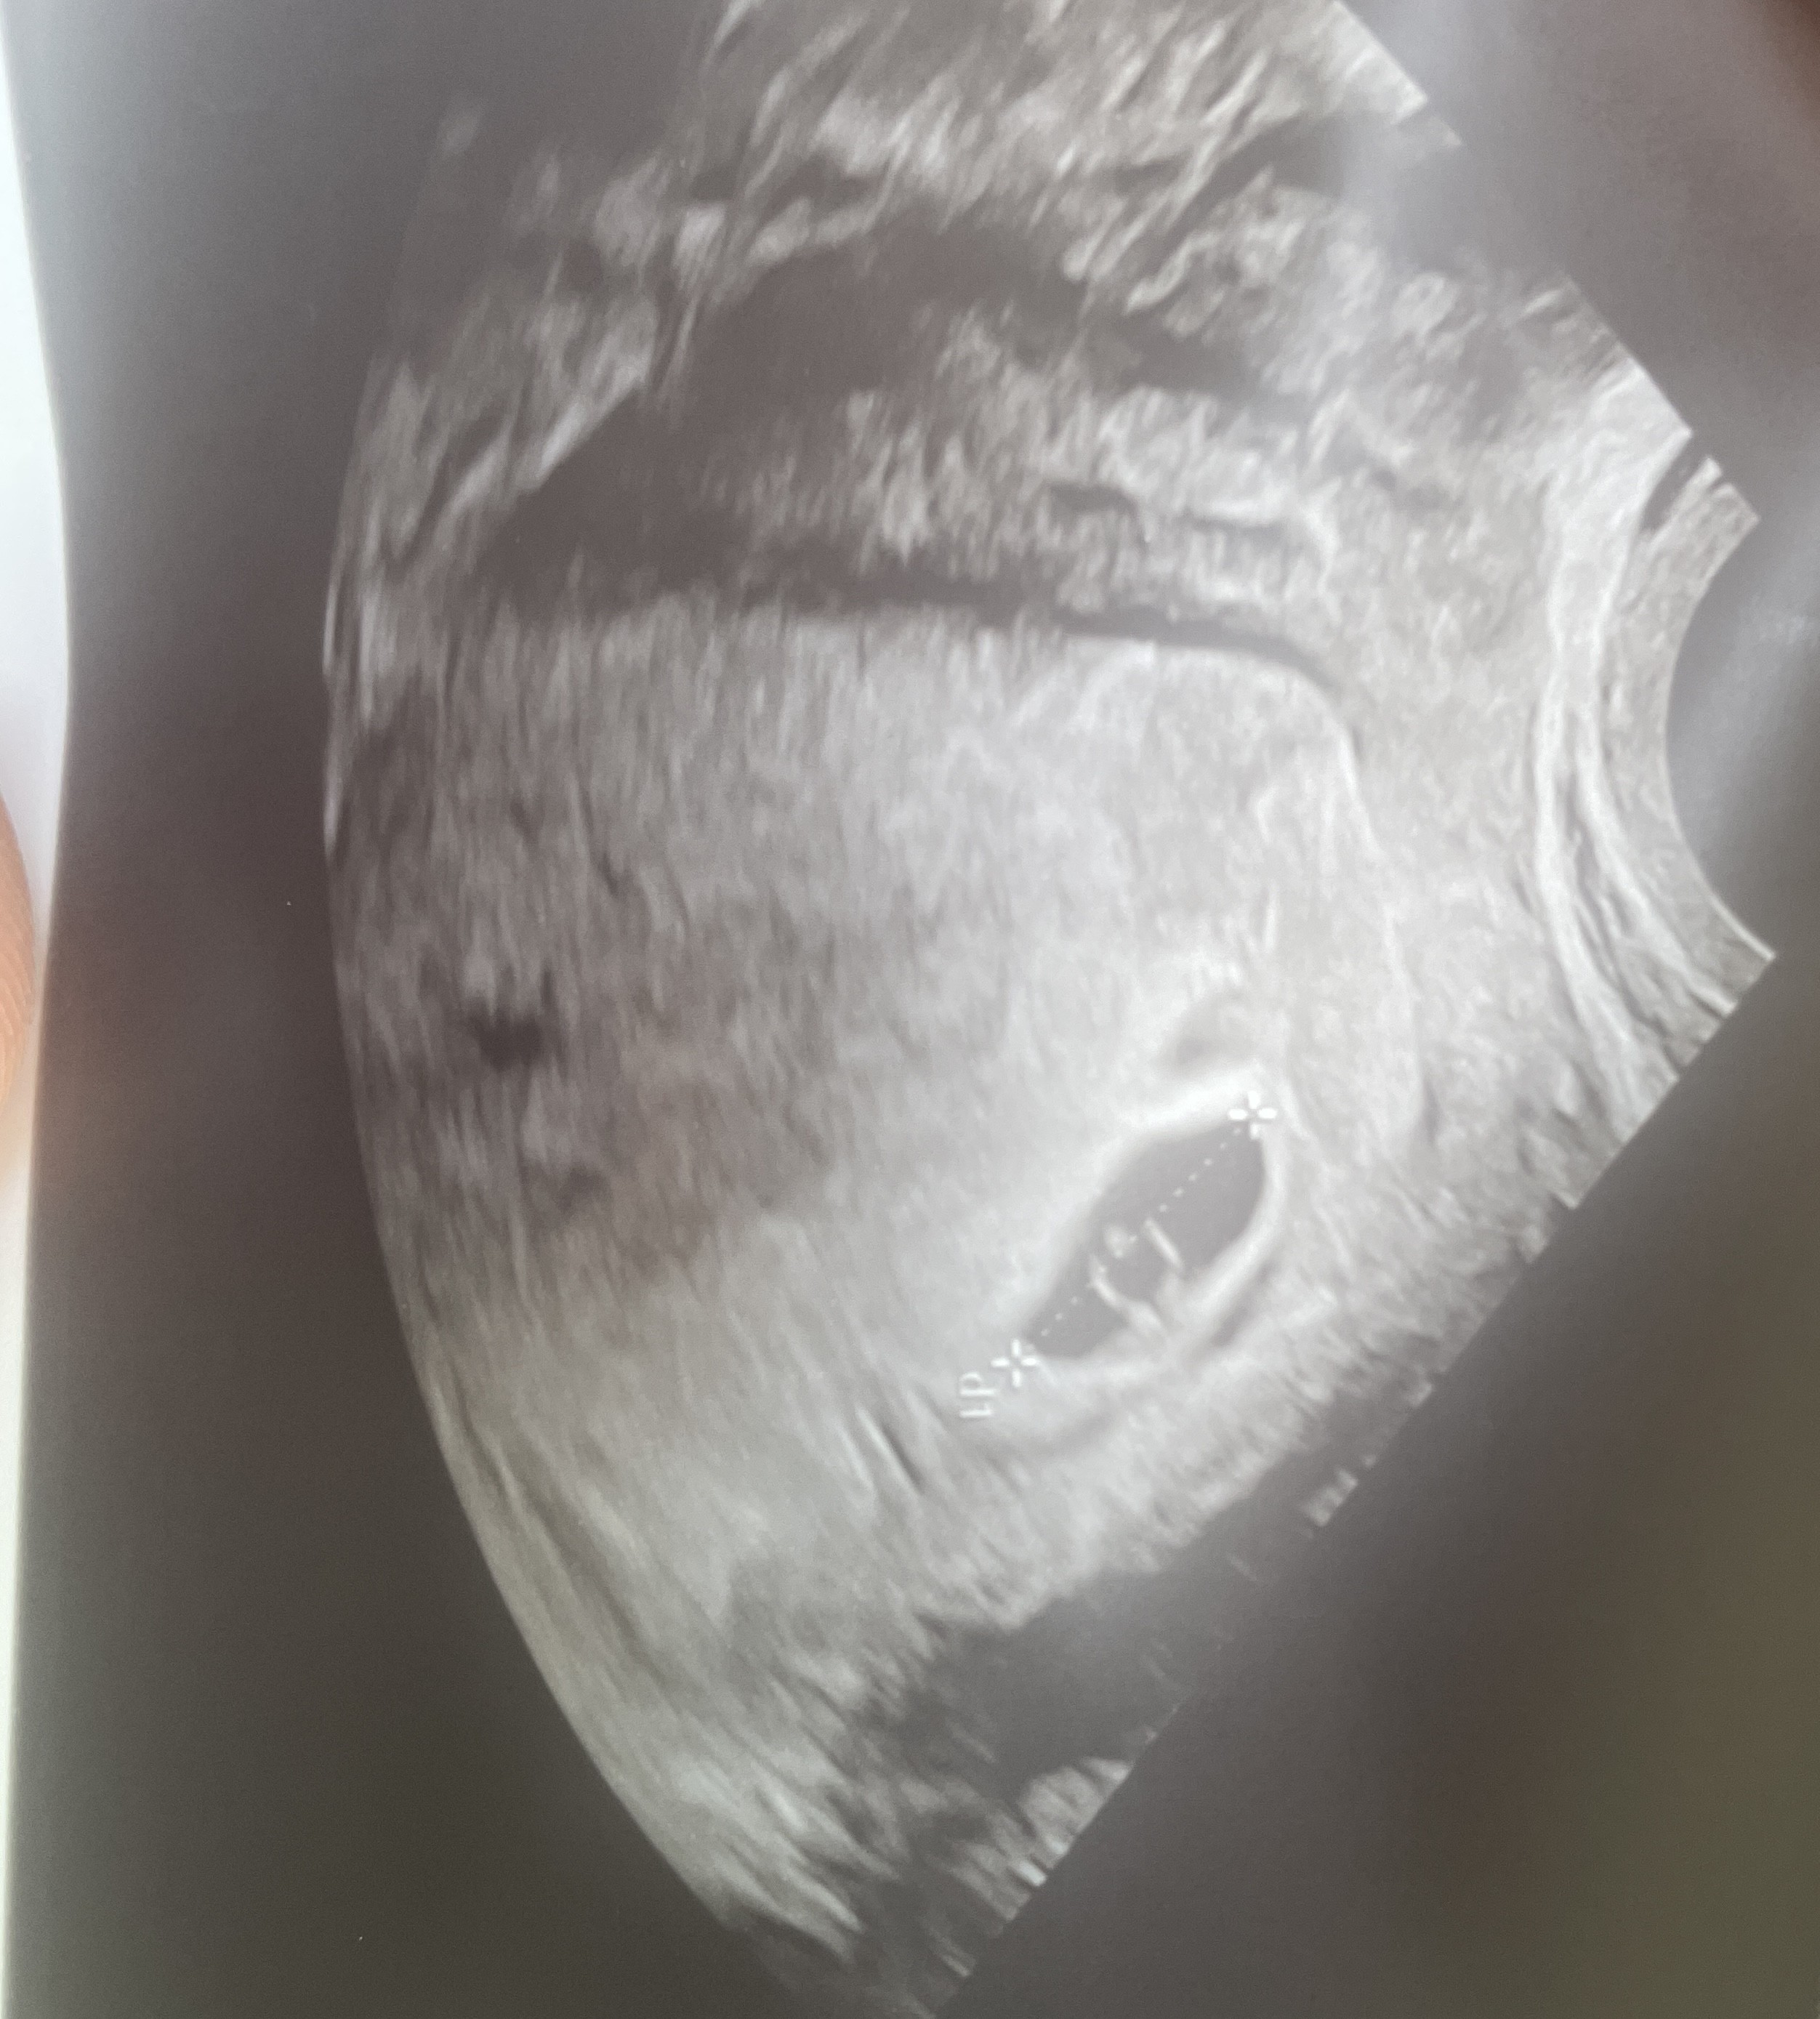

Kształt pęcherzyka ciążowego

Dziewczyny byłam dzisiaj na usg 5+3dc lekarz potwierdził obecność pęcherzyka ale powiedział że ma “dziwny kształt” podłużny. Mam czekać na kolejne usg ale martwię się. Czy któraś z was tak miała ?

Jak dla mnie wszystko jest ok. Z córką jak byłam w ciąży pęcherzyk też miał podłużny kształt 🙂

Mój pęcherzyk ciążowy miał kształt rogalika. Lekarka stwierdziła, że "nie wygląda idealnie", ale szczerze - byłam już tak zmęczona jej straszeniem, że nawet tym się nie przejęłam. Na kolejnym USG, około tygodnia później, u innego lekarza wszystko było okej.